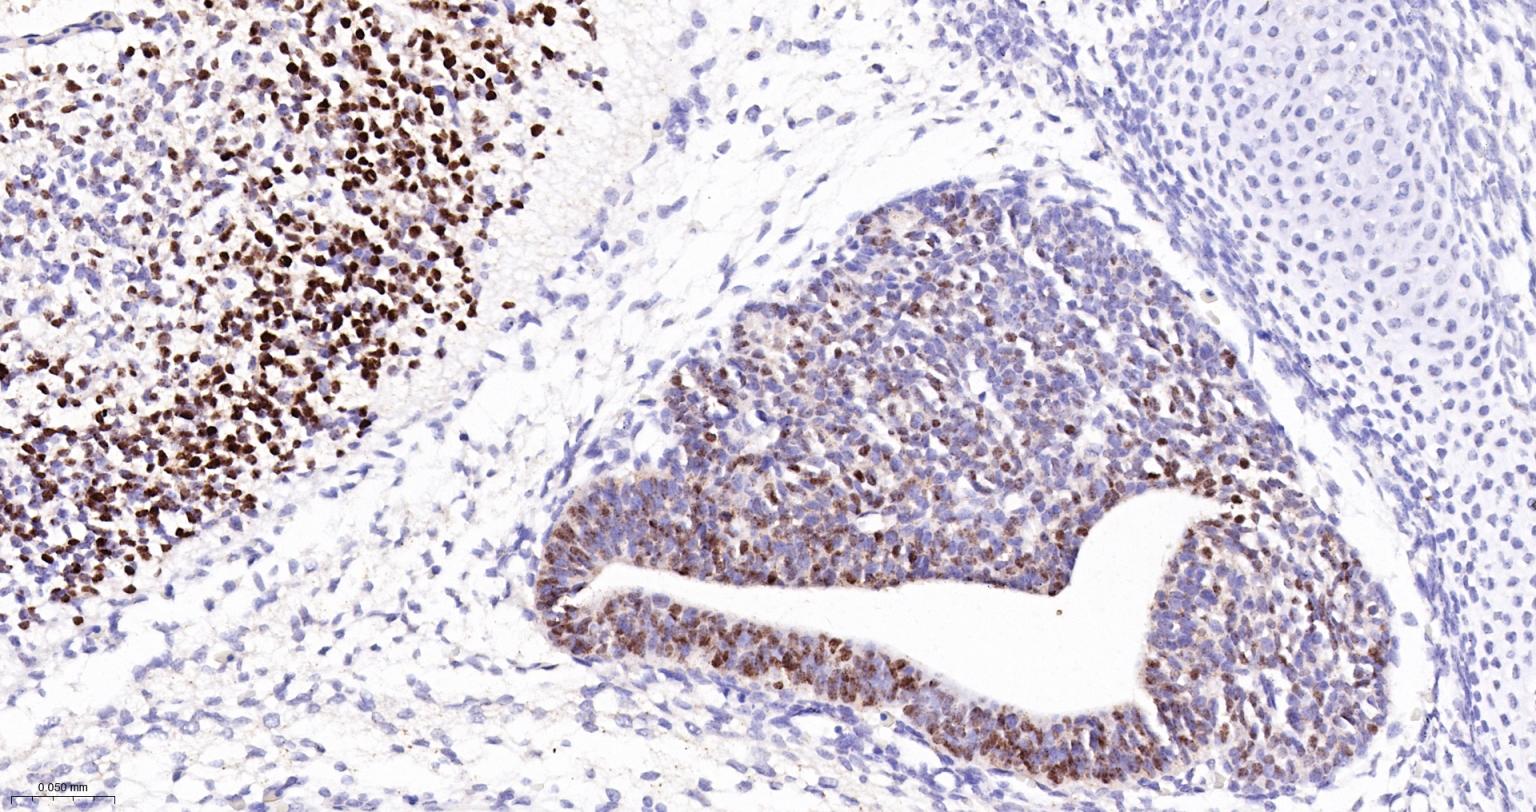

| IHC-P | Human, Mouse, Rat | 1:200-800 | |

| IHC-F | Human, Mouse, Rat | 1:200-800 | |